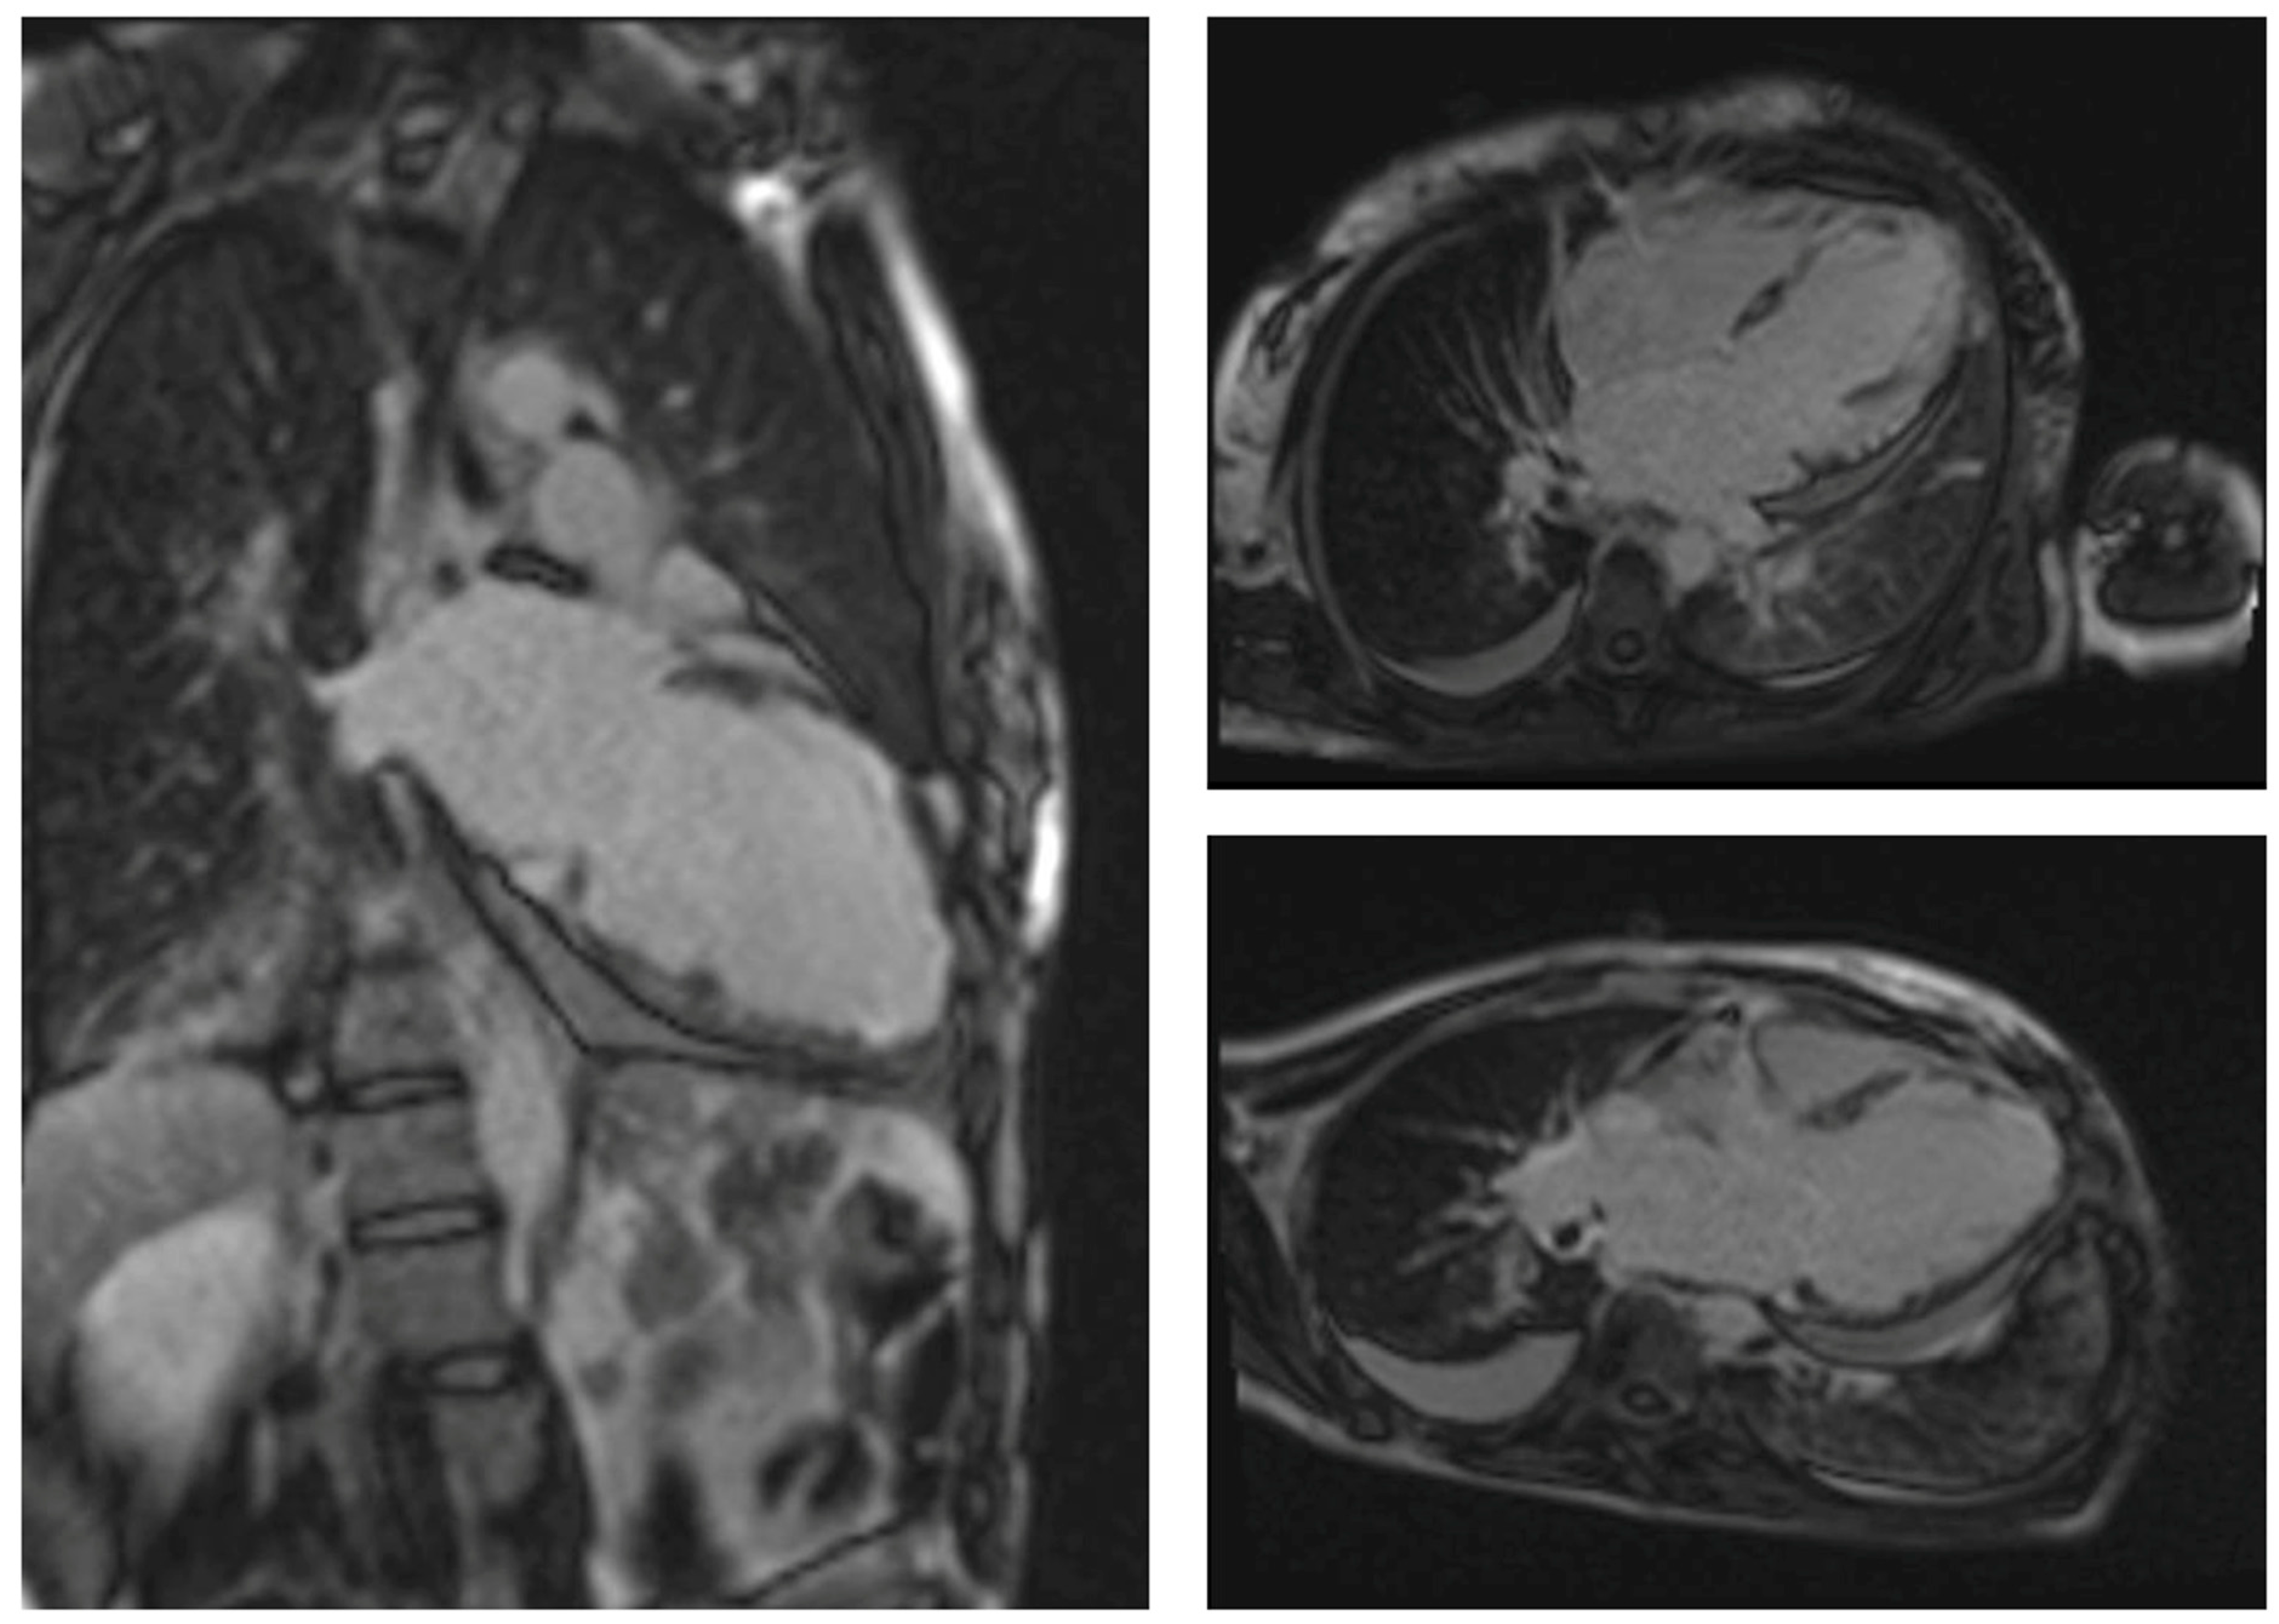

- Friedrich, M.G.; Sechtem, U.; Schulz-Menger, J.; Holmvang, G.; Alakija, P.; Cooper, L.T.; White, J.A.; Abdel-Aty, H.; Gutberlet, M.; Prasad, S.; et al. Cardiovascular Magnetic Resonance in Myocarditis: A JACC White Paper. J. Am. Coll. Cardiol. 2009, 53, 1475–1487. [Google Scholar] [CrossRef]

- Marmursztejn, J.; Guillevin, L.; Trebossen, R.; Cohen, P.; Guilpain, P.; Pagnoux, C.; Mouthon, L.; Legmann, P.; Vignaux, O.; Duboc, D. Churg-Strauss Syndrome Cardiac Involvement Evaluated by Cardiac Magnetic Resonance Imaging and Positron-Emission Tomography: A Prospective Study on 20 Patients. Rheumatology 2013, 52, 642–650. [Google Scholar] [CrossRef]

- Mavrogeni, S.; Dimitroulas, T.; Kitas, G.D. Multimodality Imaging and the Emerging Role of Cardiac Magnetic Resonance in Autoimmune Myocarditis. Autoimmun. Rev. 2012, 12, 305–312. [Google Scholar] [CrossRef]

- Markousis-Mavrogenis, G.; Sfikakis, P.P.; Koutsogeorgopoulou, L.; Dimitroulas, T.; Katsifis, G.; Giannakopoulou, A.; Voulgari, P.; Kolovou, G.; Kitas, G.D.; Mavrogeni, S.I. Cardiovascular Magnetic Resonance Reveals Cardiac Pathophysiology in Autoimmune Rheumatic Diseases. Mediterr. J. Rheumatol. 2021, 32, 15–20. [Google Scholar] [CrossRef]

- Greulich, S.; Mayr, A.; Kitterer, D.; Latus, J.; Henes, J.; Steubing, H.; Kaesemann, P.; Patrascu, A.; Greiser, A.; Groeninger, S.; et al. T1 and T2 Mapping for Evaluation of Myocardial Involvement in Patients with ANCA-Associated Vasculitides. J. Cardiovasc. Magn. Reson. 2017, 19, 6. [Google Scholar] [CrossRef]

- Lagan, J.; Naish, J.H.; Fortune, C.; Bradley, J.; Clark, D.; Niven, R.; Chaudhuri, N.; Schelbert, E.B.; Schmitt, M.; Miller, C.A. Myocardial Involvement in Eosinophilic Granulomatosis with Polyangiitis Evaluated with Cardiopulmonary Magnetic Resonance. Int. J. Cardiovasc. Imaging 2021, 37, 1371–1381. [Google Scholar] [CrossRef]

- Liu, X.; Zhou, Y.; Li, J.; Guo, T.; Lv, Z.; Zhang, D.; Feng, X.; Zhang, J.; Fang, L.; Tian, X.; et al. Cardiac Involvement in Eosinophilic Granulomatosis with Polyangiitis: Acute Eosinophilic Myocarditis and Chronic Inflammatory Cardiomyopathy. Rheumatology 2024, keae085, online ahead of print. [Google Scholar] [CrossRef]

- Fijolek, J.; Wiatr, E.; Gawryluk, D.; Nowicka, U.; Martusewicz-Boros, M.M.; Kober, J.; Piotrowska-Kownacka, D.; Roszkowski-Sliz, K. The Significance of Cardiac Magnetic Resonance Imaging in Detection and Monitoring of the Treatment Efficacy of Heart Involvement in Eosinophilic Granulomatosis with Polyangiitis Patients. Sarcoidosis Vasc. Diffus. Lung Dis. 2016, 33, 51–58. [Google Scholar]